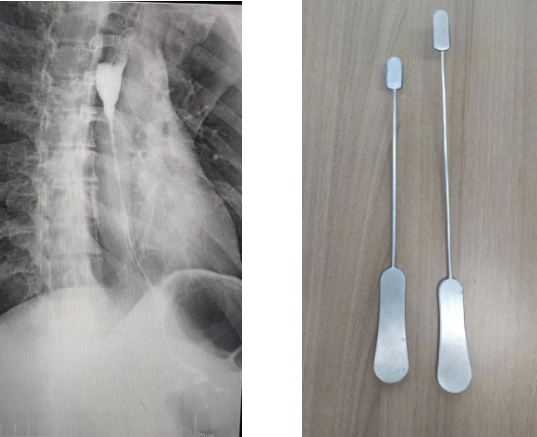

為了建立胸骨后的人工隧道,李小飛教授還自制了一把特殊的彎鉗,用于做胸骨后隧道便于將結(jié)腸順利從腹腔經(jīng)過(guò)胸骨后隧道提至頸部。